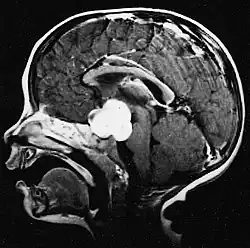

Auf -Kernspintomogrammen erscheint ein intrakranieller Tumor als massive Läsion, die nach Verwendung des Kontrastmittels lumineszierender werden kann. Eine Signalanomalie gibt es jedoch immer in -Kernspintomogrammen, die auf das Vorhandensein einer Neoplasie oder eines vasogenen Ödems hinweist. Normalerweise ist eine stärkere Lumineszenz (Kontrastverstärkung) ein Hinweis auf einen Tumor höheren Malignitätsgrades. Ein Kontrastring ist charakteristisch für ein Glioblastom, wobei der Lumineszenzanteil dem lebenswichtigen Teil des bösartigen Tumors und der dunklere -hypointense Bereich der Gewebenekrose entspricht.[4]

Das Kernspintomogramm zeigt normalerweise eine massive Kontrastverstärkungsläsion, an der das Kleinhirn beteiligt ist. Wie oben erwähnt, hat das Medulloblastom eine hohe Neigung, die Leptomeninges lokal zu infiltrieren sowie sich durch den Subarachnoidalraum auszubreiten, und bezieht dabei die Ventrikel, die zerebrale Konvexität und die leptomeningealen Oberflächen der Wirbelsäule mit ein. Folglich ist es notwendig, die gesamte kraniospinale Achse in Resonanz zu bringen.

Die Patienten leiden an einer Vielzahl charakteristischer Symptome einer fokalen oder multifokalen massiven Läsion. Das Kernspintomogramm zeigt normalerweise Tumoren mit homogener Kontrastverstärkung innerhalb der tiefen periventrikulären weißen Substanz. Multifokalität und inhomogene Verstärkung sind typisch für Patienten mit geschwächtem Immunsystem. Extrem wichtig ist die Analyse des ZNS-Lymphoms bei der Differentialdiagnose von Hirnneoplasien. Es sollte beachtet werden, dass die Verabreichung von Kortikosteroiden zum vollständigen Verschwinden der Verstärkung führen kann, was Diagnose der Läsionen erschwert. Wenn das ZNS-Lymphom in der Differentialdiagnose berücksichtigt werden soll, sollten folglich Kortikosteroide vermieden werden, es sei denn, der Masseneffekt verursacht ein ernstes und unmittelbares Problem beim Patienten.